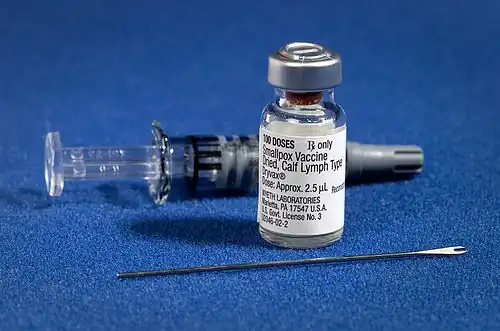

The smallpox vaccine diluent in a syringe alongside a vial of Dryvax dried smallpox vaccine and bifurcated needle | |

The first-generation vaccines are manufactured by growing live vaccinia virus in the skin of live animals. Most first-generation vaccines are calf lymph vaccines that were grown on the skin of cows, but other animals were also used, including sheep.[16] The development of freeze-dried vaccine in the 1950s made it possible to preserve vaccinia virus for long periods of time without refrigeration, leading to the availability of freeze-dried vaccines such as Dryvax.[18][19]: 115

The vaccine is administered by multiple puncture of the skin (scarification) with a bifurcated needle that holds vaccine solution in the fork.[20] The skin should be cleaned with water rather than alcohol,[20] as the alcohol could inactivate the vaccinia virus.[19]: 292 [21] If alcohol is used, it must be allowed to evaporate completely before the vaccine is administered.[19]: 292 Vaccination results in a skin lesion that fills with pus and eventually crusts over. This manifestation of localized vaccinia infection is known as a vaccine "take" and demonstrates immunity to smallpox. After 2–3 weeks, the scab will fall off and leave behind a vaccine scar.[22]

A major contribution to smallpox vaccination was made in the 1960s by Benjamin Rubin, an American microbiologist working for Wyeth Laboratories. Based on initial tests with textile needles with the eyes cut off transversely half-way he developed the bifurcated needle. This was a sharpened two-prong fork designed to hold one dose of reconstituted freeze-dried vaccine by capillarity.[138] Easy to use with minimum training, cheap to produce ($5 per 1000), using one quarter as much vaccine as other methods, and repeatedly re-usable after flame sterilization, it was used globally in the WHO Smallpox Eradication Campaign from 1968.[19]: 472–73, 568–72 Rubin estimated that it was used to do 200 million vaccinations per year during the last years of the campaign.[138] Those closely involved in the campaign were awarded the "Order of the Bifurcated Needle". This, a personal initiative by Donald Henderson, was a lapel badge, designed and made by his daughter, formed from the needle shaped to form an "O". This represented "Target Zero", the objective of the campaign.[139]